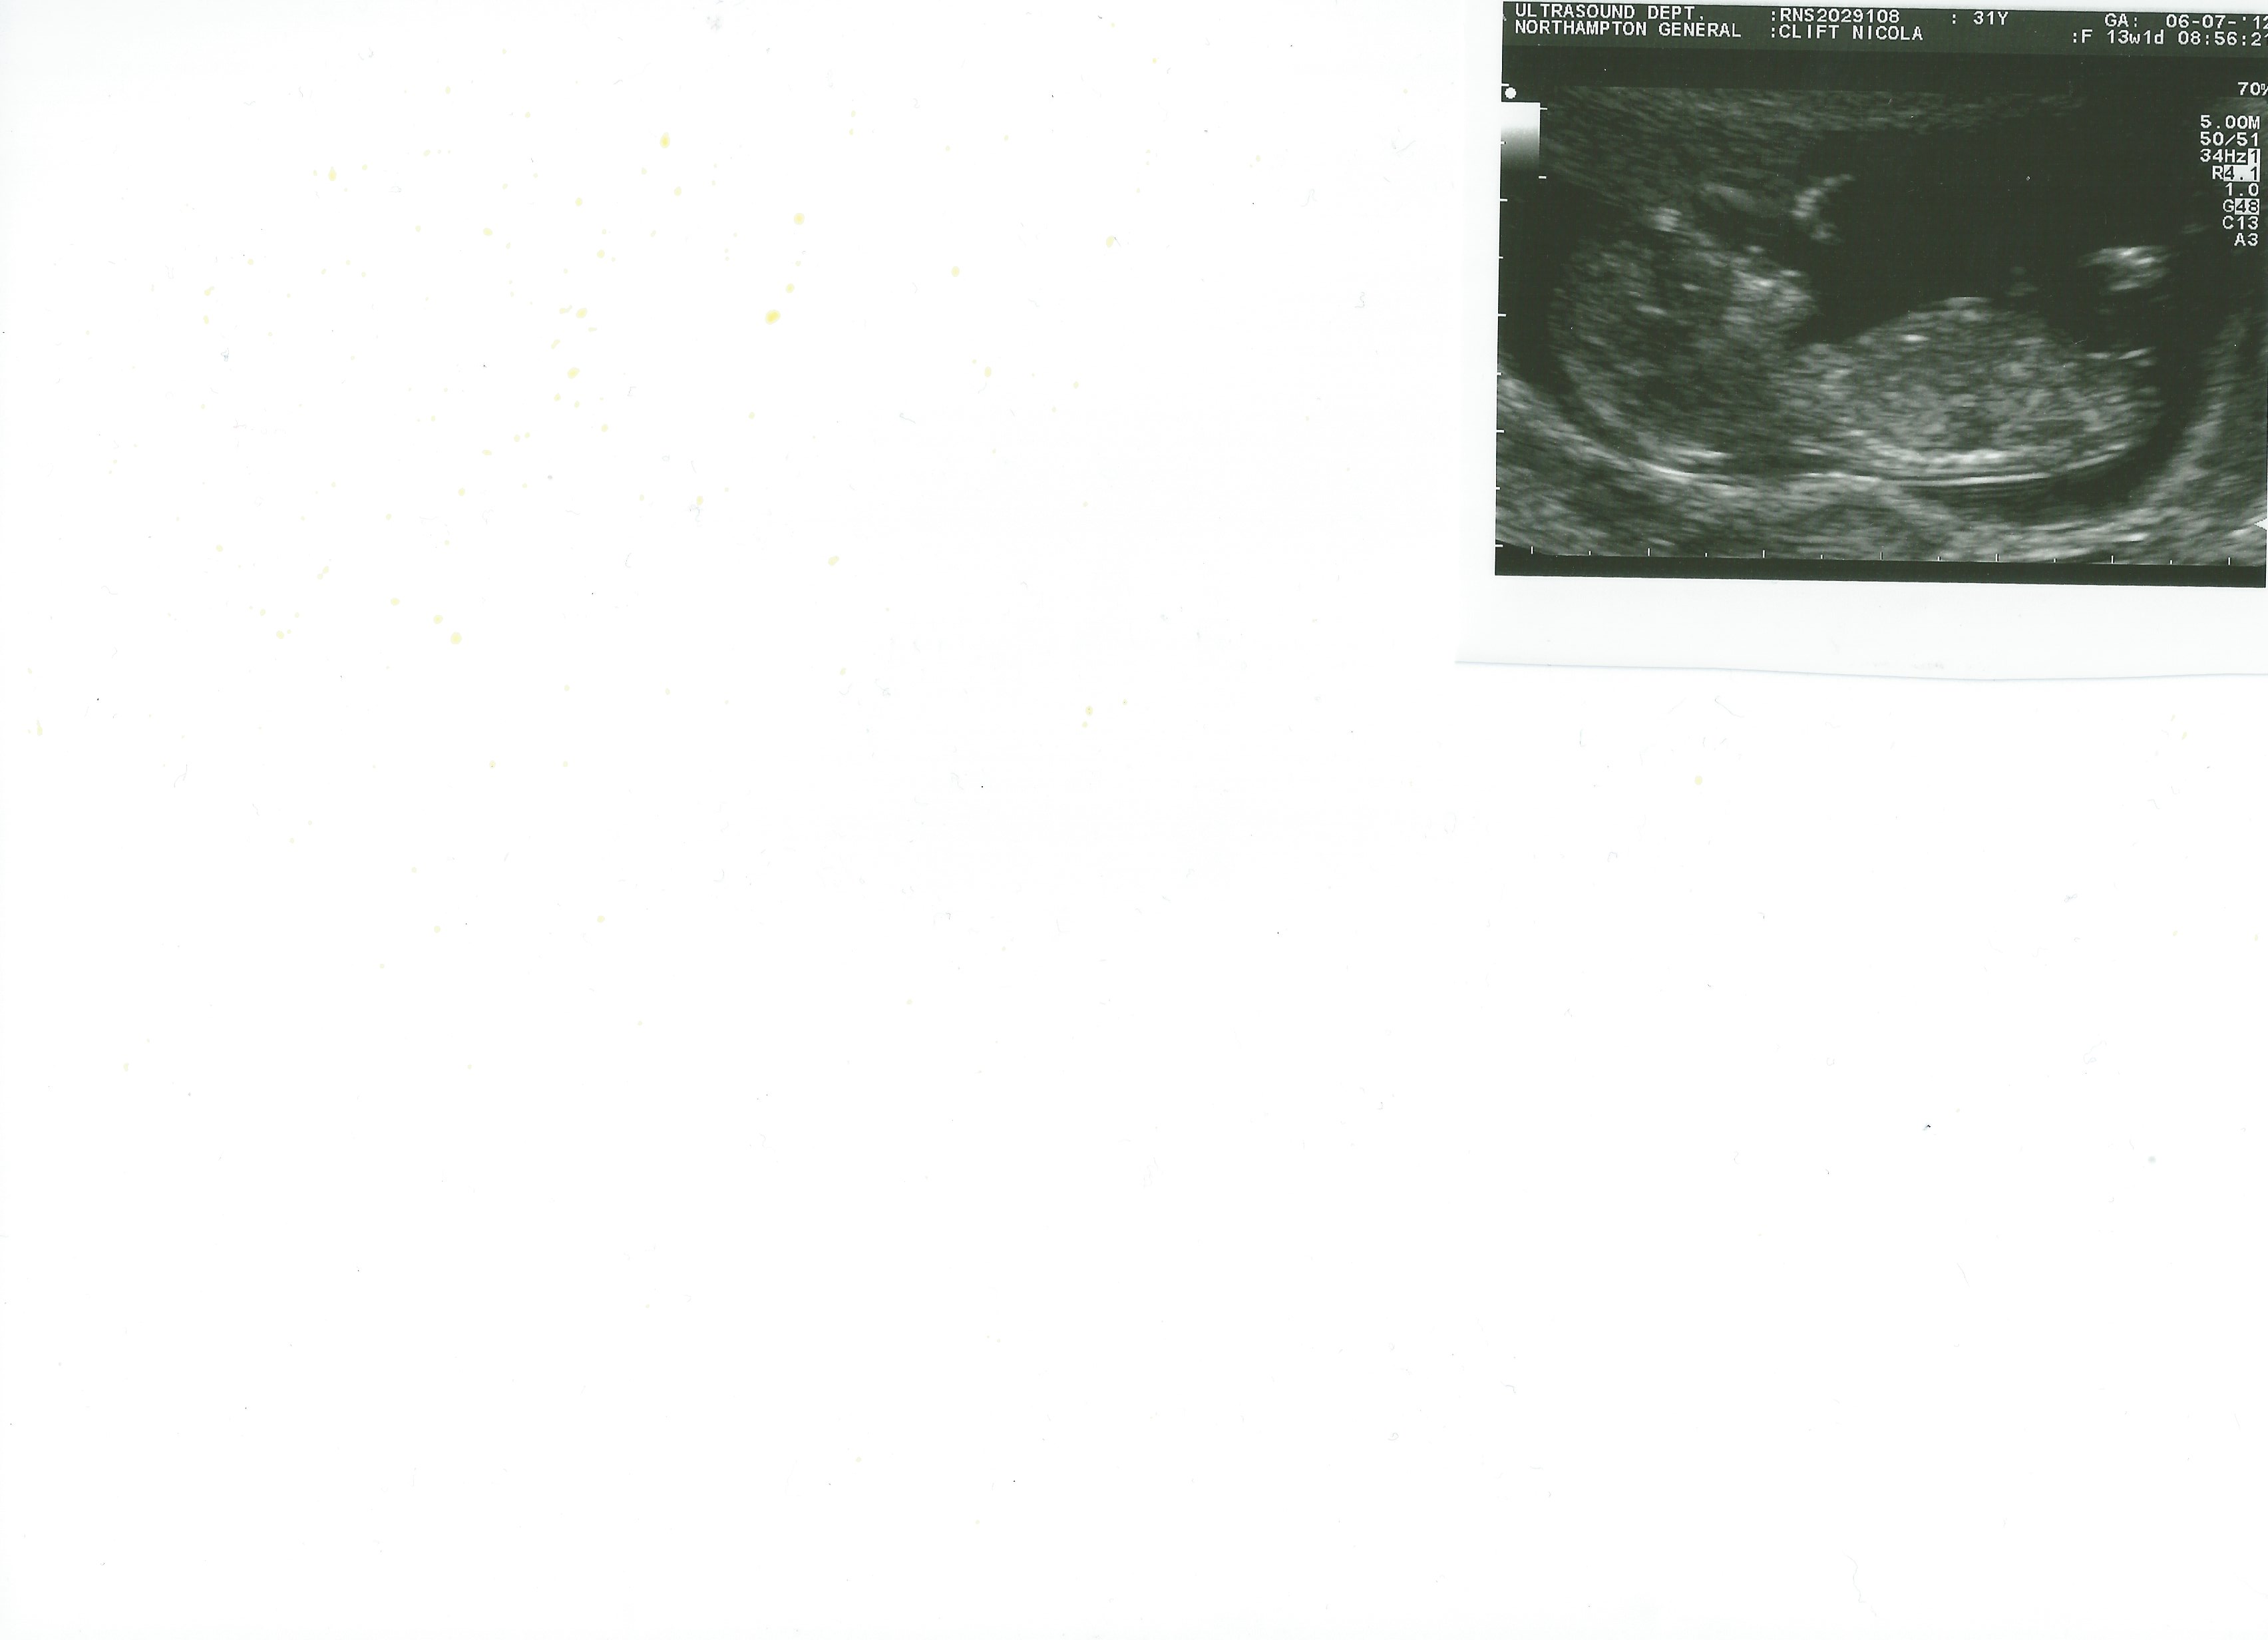

These are my 13wks 1 day scan pics.. Can anyone see the nub?